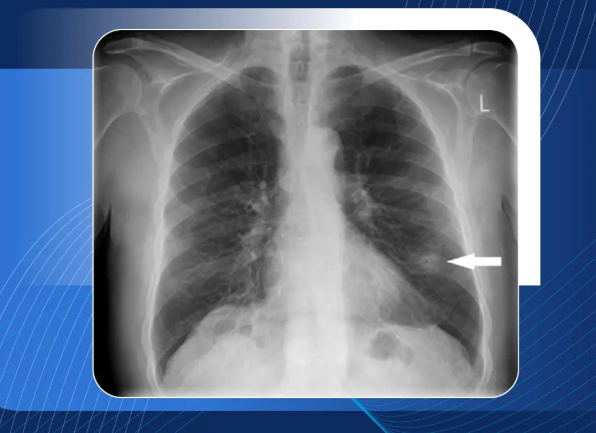

'폐결절이란' 폐 안에서 발견되는 작고 둥근 모양의 음영이나 덩어리를 말합니다. 보통 건강검진에서 흉부 CT나 X-ray를 통해 우연히 발견되는 경우가 많죠. 대부분은 3cm 이하의 크기를 가지며, 크기가 작을수록 양성(즉, 암이 아닌 경우)일 가능성이 높다고 알려져 있습니다.

결절이라는 말 자체는 '덩어리'라는 의미를 포함하고 있지만, 반드시 악성 종양(암)을 뜻하는 것은 아닙니다. 실제로 폐결절이 발견되더라도 전체의 60~80%는 양성이라는 통계도 있습니다. 이 말은 즉, 크기나 모양이 특별히 의심스럽지 않다면 무조건적인 공포는 내려놓아도 된다는 뜻이기도 하죠.

제 경우도 크기는 5mm 미만이었고, 특별한 증상 없이 발견된 경우였기 때문에 의료진은 '추적 관찰'을 권유했습니다. 단지 '지켜보는 것'만으로도 충분한 경우가 많다는 사실은 의외이면서도 안심이 되는 부분이었습니다.